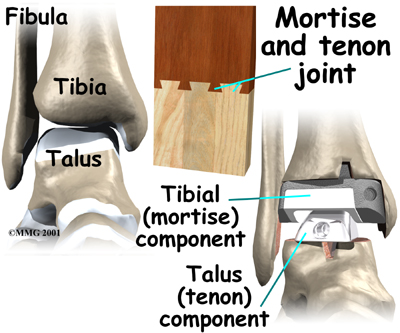

The ankle joint is made up of three bones: the lower end of the tibia (shinbone), the fibula (the small bone of the lower leg), and the talus, the bone that fits into the socket formed by the tibia and fibula. The talus sits on top of the calcaneus (the heelbone). The talus moves mainly in one direction. It works like a hinge to allow your foot to move up and down.

The artificial ankle

Each artificial ankle prosthesis is made of two parts:

- The tibial component is the part of the artificial joint that replaces the socket portion of the ankle (the top section).

- The talus component replaces the top of the talus.

The tibial component is usually made up of two parts: a flat metal piece called a metal tray that is attached directly to the tibia bone, and a plastic cup that fits onto the metal piece, forming a socket for the artificial ankle joint. The talus component is made of metal and fits into the socket of the tibial component.